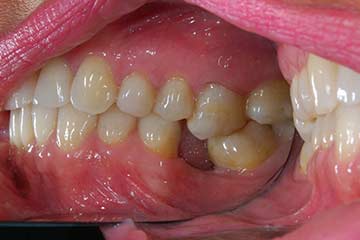

Trattamento ortodontico nell'adulto con intrusione del I° molare superiore mediante l'utilizzo di mini impianti

Trattamento ortodontico nell'adulto